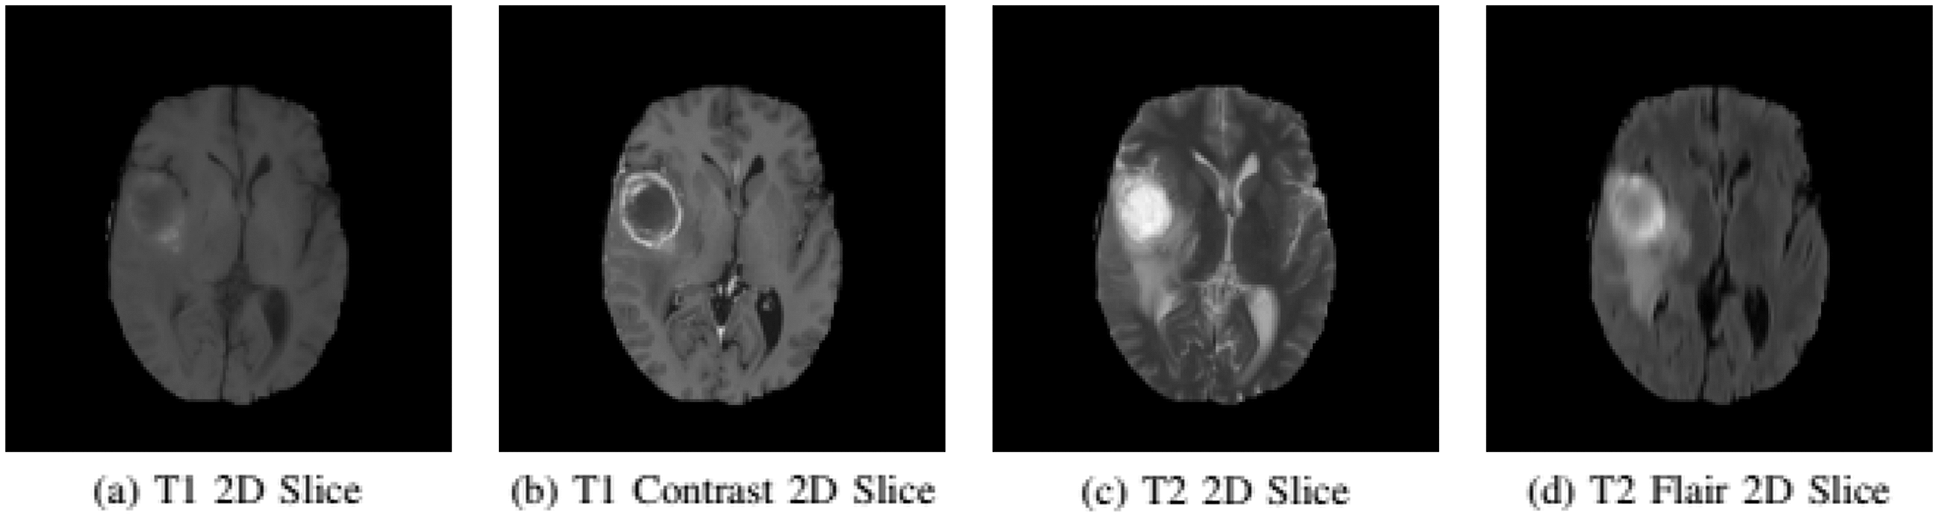

The experiments are conducted on the BRATS 2015 training database [5,38]. BRATS dataset has both real patient data and synthetic data along with their ground truth. The dataset is divided into two parts Low-Grade Gliomas (LGG) and High-Grade Gliomas (HGG) with LGG being less aggressive than HGG. There are 220 samples of HGG and 54 samples of LGG. Each sample of the patient has four modalities namely T1, T1 Contrast (T1c), T2, and T2 FLAIR. In T1 modality, tissues with high-fat content appear bright and compartments filled with water appear dark. In T1c modality has high contrast in comparison to T1 modality other than that both modalities are similar. In T2 modality, compartments filled with water appear bright and high-fat content appears dark. Whereas, T2 FLAIR is similar to T2, but with comparatively longer Echo Time (TE) and Repetition Time (TR). First, we conduct experiments on HGG because samples of necrosis and enhancing tumor are small in the LGG dataset. Figs. 2a–2d gives a visual of all four MRI modalities.

Figure 2: Imaging modalities in BRATS 2015 dataset